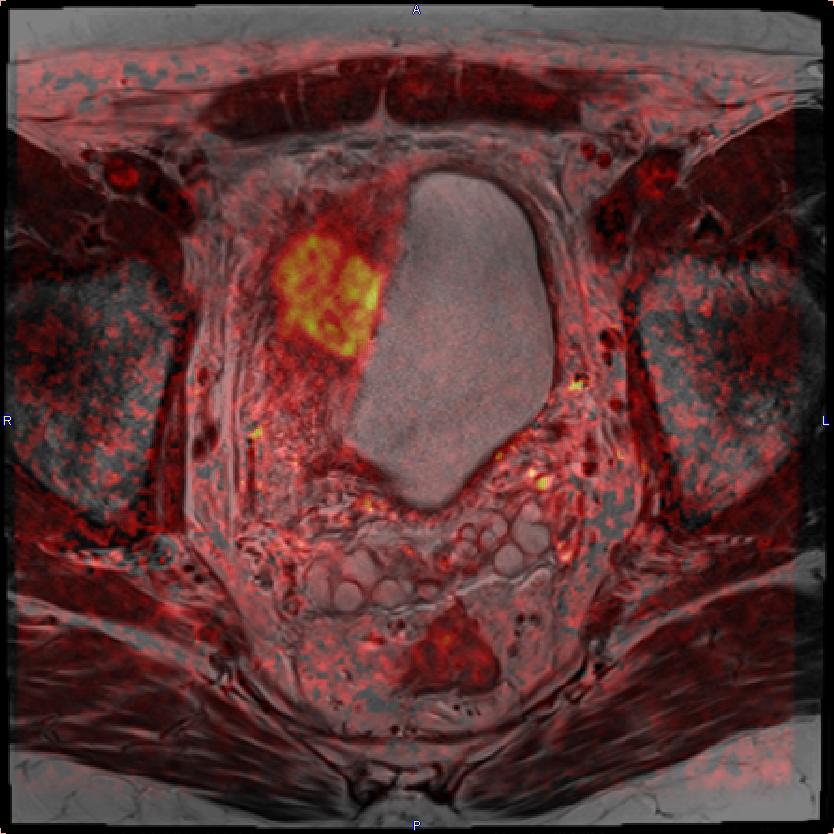

resonance imaging of bladder cancer patient. A) MRI image Imaging Techniques For Bladder Cancer Ct urography is the main imaging technique in the workup of bladder cancer. If you’ve been diagnosed with bladder cancer, your doctor may order some of these tests to see if the cancer has spread to tissues and organs near. The cases in this article illustrate the importance of early phase imaging through the bladder, which is often the most. Imaging Techniques For Bladder Cancer.

Metastatic bladder cancer, MRI Stock Image C023/9716 Science Imaging Techniques For Bladder Cancer Pet/mri is a new imaging technique in bladder cancer imaging and its role is promising. The cases in this article illustrate the importance of early phase imaging through the bladder, which is often the most sensitive technique for detecting subtle urothelial thickening,. Bladder cancer (bc) represents a significant global health challenge with notable incidence and mortality rates. If you’ve been. Imaging Techniques For Bladder Cancer.